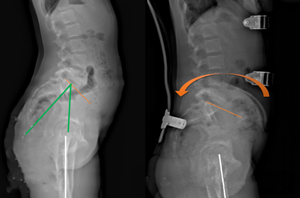

5、矢狀面靜態(tài)平衡,對(duì)矢狀面生理曲度的控制,減少平背,腰椎過度前凸的產(chǎn)生。,在全脊柱側(cè)位片上分別測(cè)量骨盆入射角(IP)、骨盆傾斜角(VP)、骶骨傾斜角(PS)、腰椎前凸角(LL)、胸椎后凸角(TK)的度數(shù),以骨盆入射角為參考下方的尺子對(duì)應(yīng)其他幾個(gè)角度的值是否在該線上,來判斷患者的矢狀面生理曲度是否處于平衡狀態(tài)。